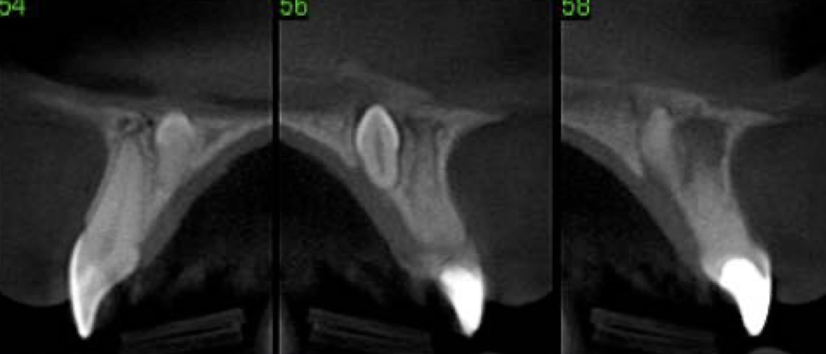

What dental anomaly is this?

dilaceration